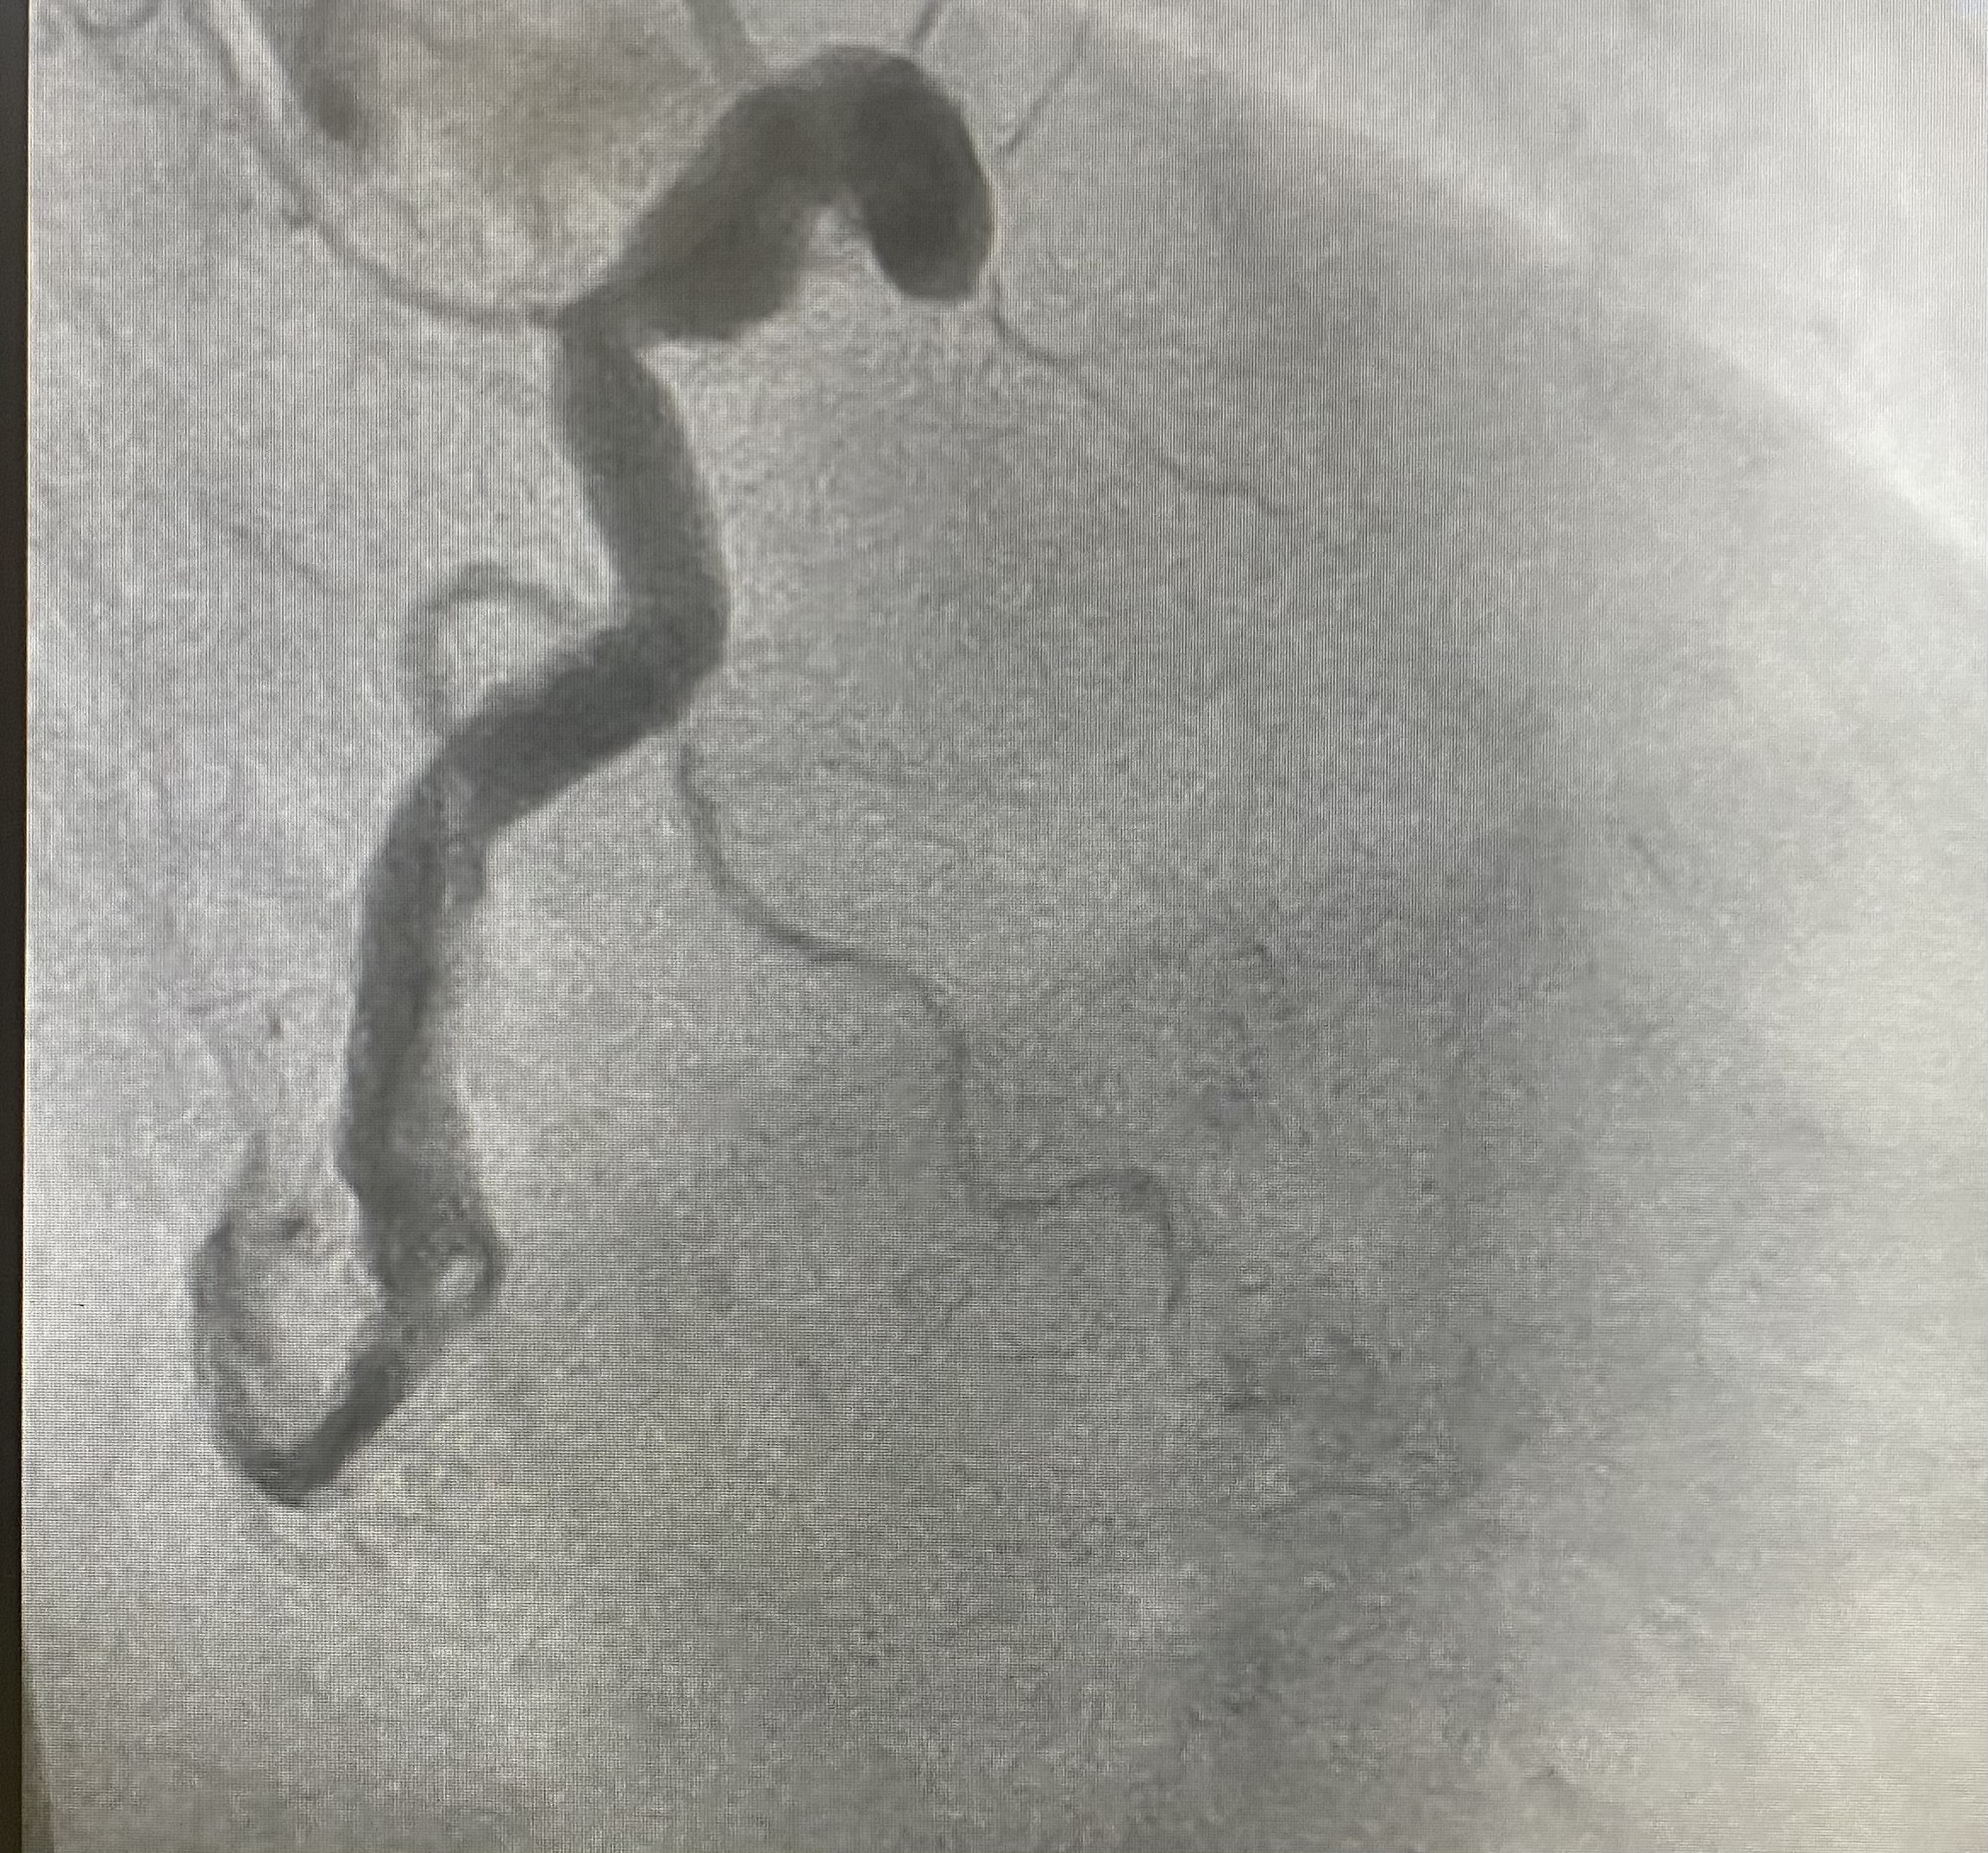

Introdução: O aneurisma de artéria coronária é definido como uma dilatação focal do diâmetro arterial superior a uma vez e meia o diâmetro do vaso normal. O estudo histológico demonstra hialinização difusa, depósitos de lipídios, ruptura da íntima, calcificação da média, fibrose focal e hemorragia intramural. Essas áreas, mesmo se não associadas à estenose, estão sujeitas a espasmos, tromboses, embolias e dissecções espontâneas, que são potenciais causas de síndromes coronarianas agudas. A prevalência na literatura em pacientes submetidos à coronariografia varia entre 0,15% e 4,9%. O que se sabe sobre sua patogenia, além da suscetibilidade genética e da associação com doença aterosclerótica, é que também são correlacionadas à outras doenças como Kawasaki, Marfan,pós-infecciosa e iatrogênica após manipulação intracoronária.Relato de caso:M.R.F.S., mulher, 63 anos, HAS e tabagista, quadro de precordialgia típica com 5 horas de duração, sudorese fria e hipotensão, trombolizada na origem sem critérios de reperfusão, onde apresentou PCR, revertida após 4 ciclos. Admitida em nosso serviço comdrogas vasoativas. ECG com supra ST em parece inferior (imagem 1). ECOTT com Acinesia inferosseptal,DSVE moderado (FEVE 31% - Simpson). Hemodinâmica: TCE bifurcado, observa-se aneurisma estendendo-se para terço proximal de ADA e ramo diagonal, sem lesões obstrutivas. Ramo Dg exibe grande aneurisma em terço proximal , isento de estenoses. ACD (dominante)exibe aneurisma difuso, do terço proximal ao médio com imagem negativa em terço médio sugestiva de trombo luminal e imagem focal, em segmento médio distal, sugestiva de lesão instável (napking ring- imagem 2). O fluxo do meio de contraste através de ACD e seus ramos tem aspecto normal.Paciente evolui a óbito após dois dias. Discussão/Conclusão: Esse caso ilustra uma manifestação típica de aneurisma de artéria coronária com trombose luminal. A estratégia terapêutica adotada foi a anticoagulação. O tratamento dos aneurismas coronários envolve terapia de antiagregação plaquetária e anticoagulação. Os aneurismas muito grandes e/ou multiarteriais têm sido tratados com enxertos vasculares coronários.Existem poucas descrições cirúrgicas para o tratamento de aneurismas das artérias coronárias, permanecendo controvérsias sobre a melhor opção terapêutica, demonstrando a necessidade de se realizar mais estudos sobre o tema.

Img.2